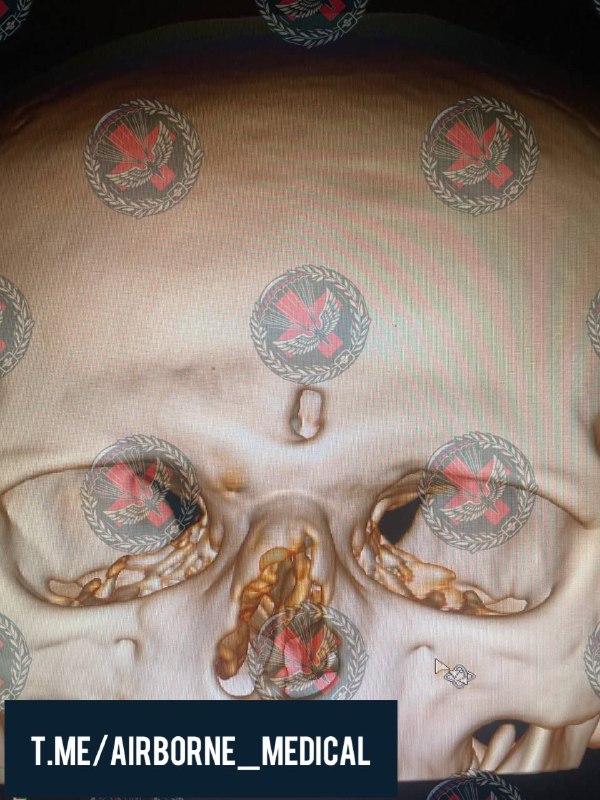

2024-08-24 16:33:06

Осколочное ранение глаза

В ходе диагностики было обнаружено 2 осколка: внутриглазной и предположительно вколоченный в склеру.

Интраоперационно проведена ревизия склеры, диагноз подвержен

Выполнено:

- ПХО проникающего ранения

- удаление вколоченного инородного тела

В течение 2-х недель предстоит ещё один этап хирургии, сохраняется шанс на предметное зрение

Фото:

1 - КТ головы, ВГИТ правого глаза

2 - внешний вид глаза перед ПХО

3 - конъюнктива ушита после ПХО, швы удаляются через 7-14 дней